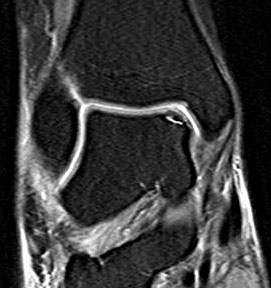

Abbildung 13-14, Video 7

Osteochondrale Läsion an der rechten medialen Talusschulter. Die Knorpelfläche erscheint bei der initialen Inspektion häufig intakt, erweist sich dann bei der Tasthakenpalpation allerdings als deutlich weicher verglichen mit dem umliegenden intakten Knorpelgewebe. In den meisten Fällen lässt sich mit dem Tasthaken ein Riss in der Oberfläche nachweisen und eine lose chondrale bzw. osteochondrale Schuppe abheben. Die instabilen Knorpelanteile und die sklerotisch veränderten Anteile der subchondralen Knochenschicht müssen mit einer Kürette oder einem Shaver entfernt werden, bis ein stabiler Rand aus gesundem Knorpelgewebe besteht. Die Eröffnung des subchondralen Knochens erfolgt mit einer gebogenen Ahle. Anschließend (ggf. nach dem Öffnen der Blutsperre) sollten kleine Blutungen aus den Knochenkanälen erkennbar sein.